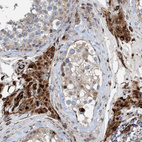

Immunohistochemical staining of human testis shows positivity in Leydig cells.